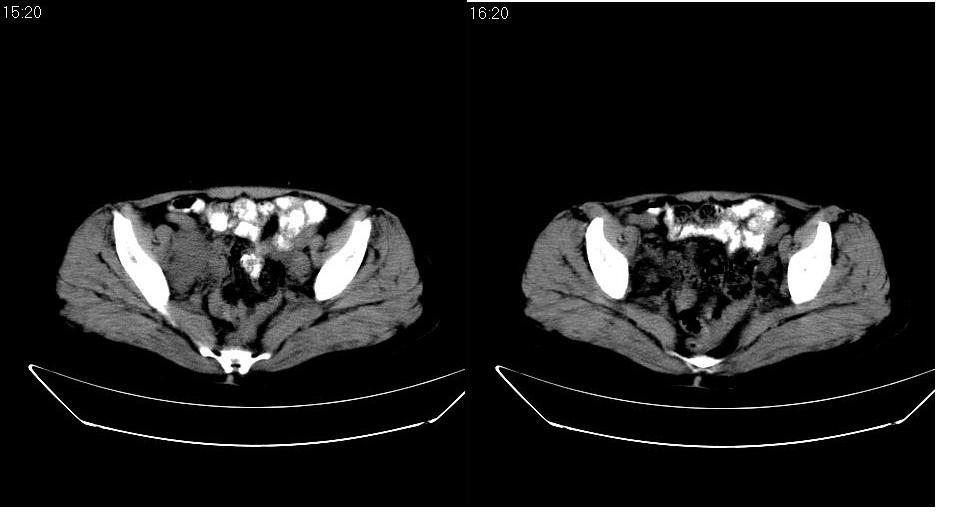

腹膜后多发肿大淋巴结肿大并融合改变;右侧回盲部可见团块样软组织影,不规则;

腹膜后诸多淋巴结,右侧髂窝软组织块影,综合患者大便次数、形状改变,考虑结肠回盲部肿瘤

盆腔内的肿块与升结肠没有什么关系,我考虑1来于小肠 2就是个融合的盆腔淋巴结 不能解释的是病人为什么大便变细,黏液便,会不会是直肠有浸润,我看直肠壁好象有点厚

回盲部可见团块样软组织影,不规则;腹膜后多发肿大淋巴结肿大并融合改变;考虑回盲部肿瘤并腹膜后淋巴结转移,建议钡剂灌肠或增强检查.

双侧盆腔均可见不规则形软组织肿块影,似为结节状影融合而成,但以右侧为甚,腹主动脉与下腔静脉周围亦可见多个肿大淋巴结.